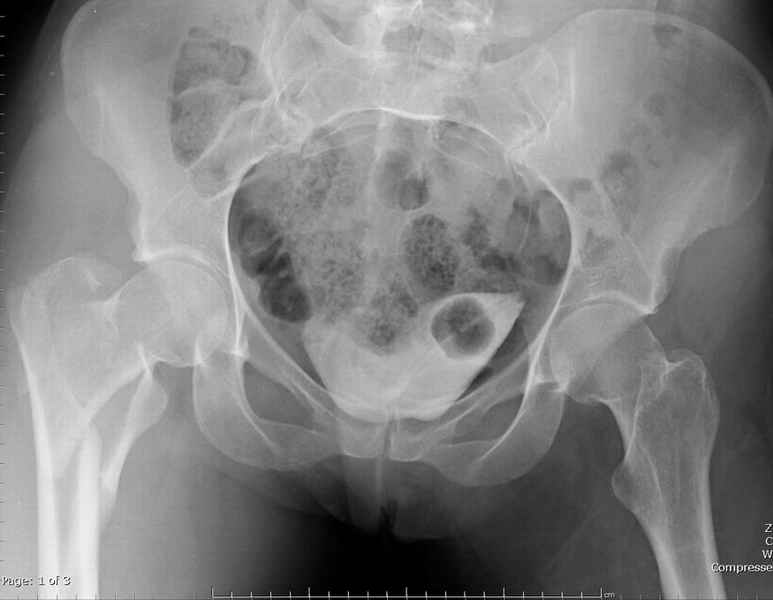

Уважаемые коллеги.Ко мне обратился мой коллега, весьма опытный травматолог, владеющий практически всеми видами остеосинтеза, с просьбой собрать мнения по поводу нескольких клинических случаев - два перелома бедра и перелом плеча.Если можно, подтвердите свое мнение иллюстрациями аналогичных ситуаций, либо ссылками - для клинического разбора. Бедро 1:Женщина 1929 г.р. Травма в результате падения 14.09.04г.Диагноз Закрытый оскольчатый чрезвертельный перелом правой бедренной кости со смещением отломков.Сопутствующие заболевания: ИБС, стенокардия напряжения, постинфарктный кардиосклероз (ИМ в 1992 году); гипертоническая болезнь 2 ст.; ожирение 3. Дополнительные данные - сохранная старушка.Спасибо.С уважением Александр Артемьев

Типичный остеопорозный вертельный перелом , не стабильный, 4-х фрагментный, базоцервикальный. Лечение оперативное не позднее 48 часов после перелома, чем раньше тем лучше, если общее состояние позволяет.

Centromedullary and Cephalomedullary По классификация Seinsheimer

(1978) V- на основе количества фрагментов-нестабильный.

По Russel- Taylor Type II – Piriformis is not intact Type IIB – lesser

troch is not intact перелом с вовлечением двух кортексов и

вертела - нестабильный,